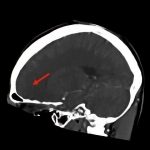

断層撮影